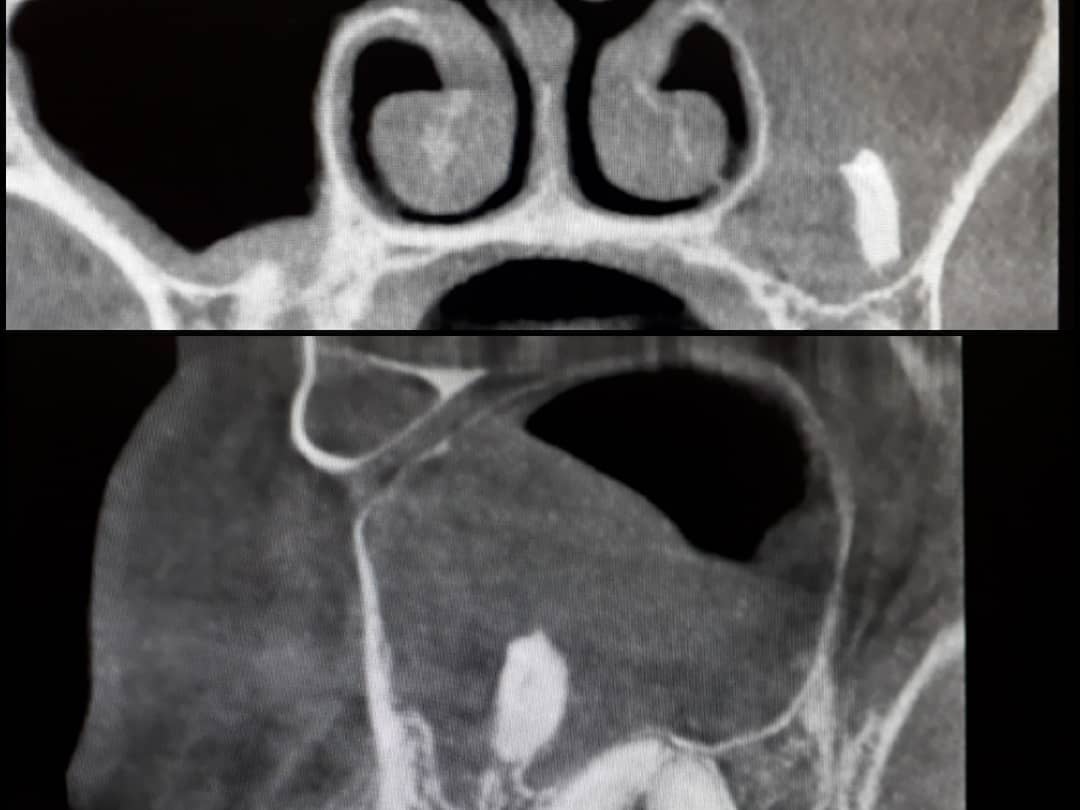

К посту врач прикрепил фото верхнечелюстной пазухи больного.